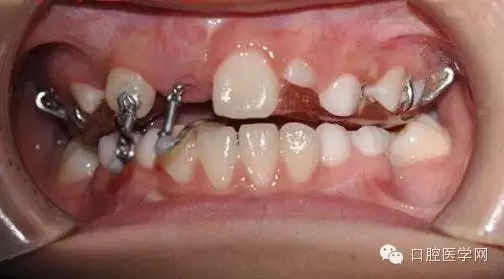

基本資料:男8歲、祖籍山東滕州、二年級(jí)。

主訴:門牙遲遲不長

現(xiàn)病史:右乳上一牙根滯留。

處理:拍片,CBCT,埋伏牙手術(shù)牽引。

埋伏牙在臨床較常見,可能于頜骨退化有關(guān),現(xiàn)以一例典型埋伏牙為例,講述簡簡單單牽引全過程,及注意事項(xiàng)。

小兒8歲發(fā)現(xiàn)右上門牙遲萌,右乳一殘根。